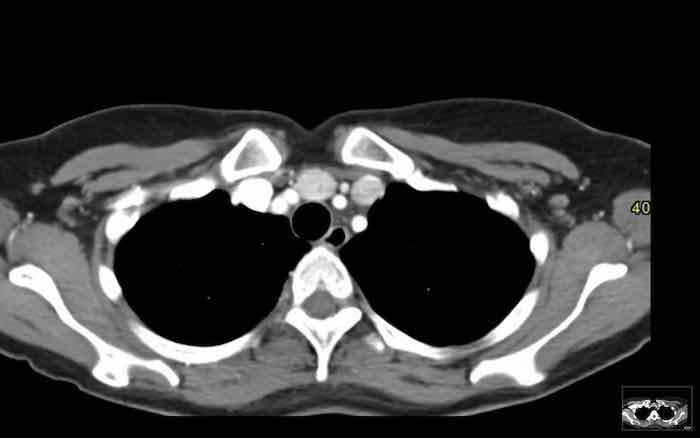

Các hình ảnh này của một bệnh nhân nam 60 tuổi có đau ngực, được chụp CT ngực để đánh giá điểm vôi hóa mạch vành.

Hãy phân tích hình ảnh trước.

Nhận định của bạn là gì?

Hình ảnh

Có một khối đặc ở trung thất và các tổn thương màng phổi.

Thảo luận

Các tổn thương màng phổi chỉ xuất hiện ở bên phải, đây là đặc điểm điển hình của di căn màng phổi kiểu “nhỏ giọt” (pleural drop metastases) của thymoma.

Chúng là kết quả của sự xâm lấn trực tiếp vào màng phổi, không phải di căn theo đường máu, và chỉ xuất hiện ở một bên.

Tiếp tục xem PET…

Hình PET cho thấy khối ở trung thất và nhiều tổn thương di căn màng phổi chỉ ở bên phải.